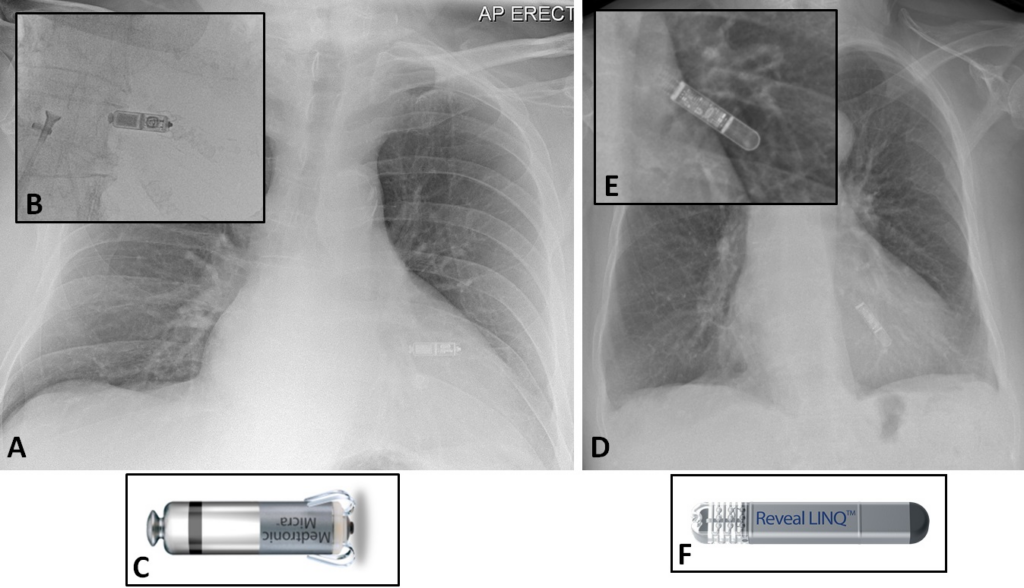

무선 심박동기 마이크라 (Micra)

- 크기 : 지름 0.67cm, 길이 2.5cm

- 시술 : 피부 절개 없이 대퇴 정맥을 통해 심장 안에 삽입 (흉터 없음.)

- 배터리 수명 : 환자에 따라 다르지만 평균 12년 정도